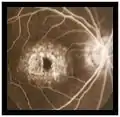

Fondo de ojo

En las primeras fases la disminución de la agudeza visual es clara, pero no se observa grandes alteraciones en el fondo de ojo. A medida que progresa la enfermedad, fragmentos ricos en lípidos se acumulan en la capa del epitelio pigmentario de la retina por debajo de la mácula, los cuales aparecen como manchas amarillentas. El epitelio pigmentario de la retina es una capa que se encuentra entre la retina y la coroides, que es la responsable de irrigar y nutrir a las células fotorreceptoras de la retina que son los conos y bastones. Estos fragmentos de lípidos se llaman lipofuscina. En los casos avanzado de la enfermedad, esta acumulación progresiva de lipofuscina provoca la atrofia de la mácula y del epitelio pigmentario de la retina.

- Angiografía con fluoresceina: muestra una coroides oscura debido a depósitos de lipofuscina dentro del epitelio pigmentario de la retina e hiperfluorescencia macular debido al efecto ventana.